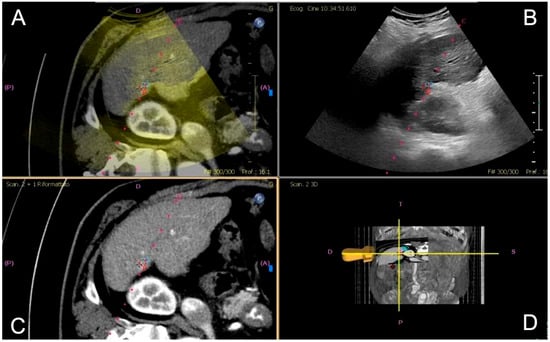

Once the microwave 13.5 G antenna (Emprint Microwave Ablation System, Medtronic, and Covidien, Boulder, CO, USA) was in place, sedation was deepened and ablation was performed with a power of either 100 or 150 W for a time established by the operator based on the tumor size and the microwave manufacturer data; all cases were ended with track ablation (Figure 2).

Figure 2. Contrast-enhanced CT (CECT) in the arterial phase demonstrates a newly diagnosed HCC located in segment VI of the liver, near the hepatic capsule. (A) The lesion shows intense arterial-phase hyperenhancement (wash-in), a typical imaging hallmark of HCC. (B) One-month follow-up CECT shows no residual enhancement, consistent with complete response to treatment. (C) CT–US fusion image following co-registration, enabling precise visualization of the lesion (highlighted by a red target). (D) The corresponding real-time US image during the ablation procedure, with the lesion and ablation needle clearly visualized (highlighted by a red target).